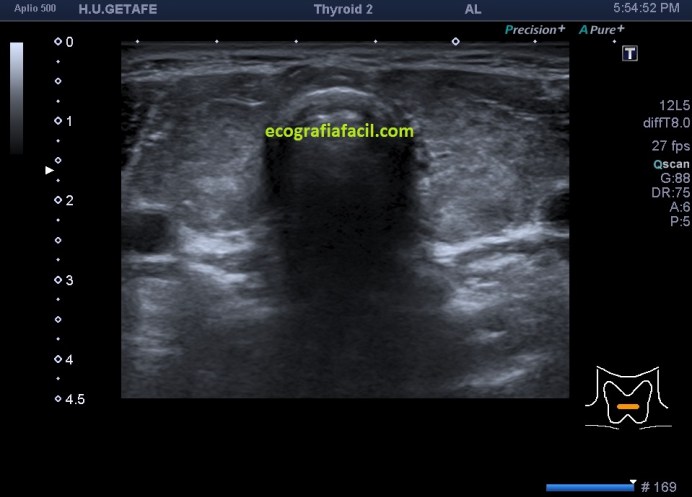

En la imagen 3, el corte axial de ambos lóbulos tiroideos afectados. Compara imagen 1 e imagen 3 y te vas a dar cuenta como a veces, en el primer segundo la exploración ya sabes que la glándula es patológica, como es la imagen 3.

3